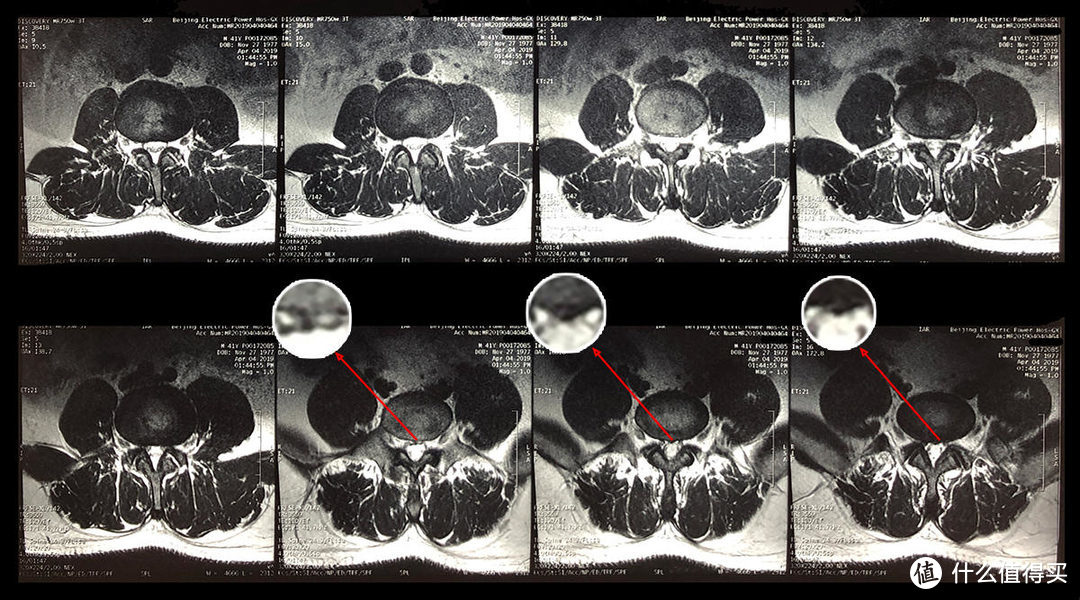

在计算机面前长时间工作而不注意保持适当的座位,而且病情非常严重,最坏的病情是躺在床上,不动不动,从开始恐慌到焦躁不动到静静接受的三年,心脏的路线可能被界定为下降和下降,与中国医生、西方医生、堕落医生进行几次医疗咨询,现有治疗结果不如理想,最终,我的妻子采用了最简单的方法成功地治愈我的问题,允许我先卖掉,然后再卖掉。